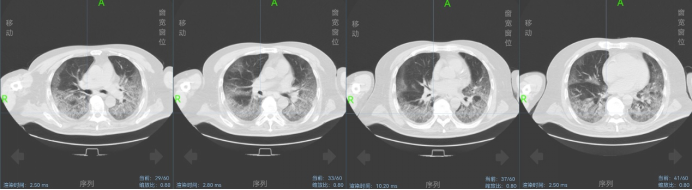

治疗过程中患者病情逐渐稳定可间断面罩吸氧过度为鼻导管吸氧,于2022年11月28日复查胸CT(图3)。病情逐渐稳定,待核酸转阴计划予以出院。

图3  2022年11月28日胸部CT